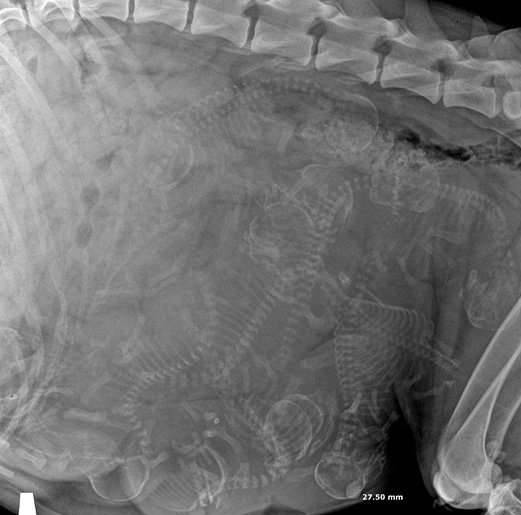

▼怀孕的狗狗